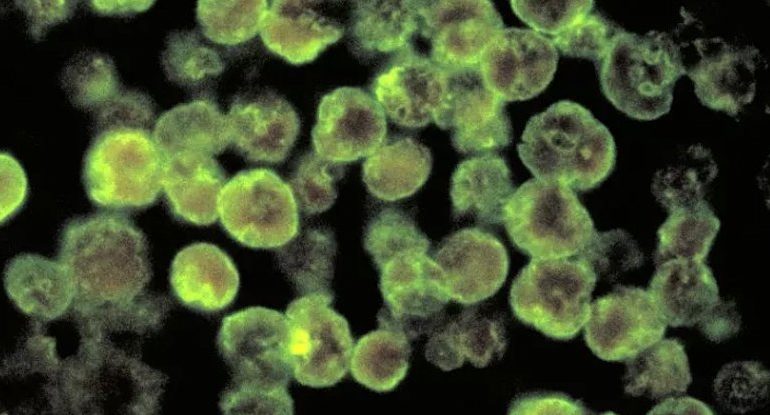

Deadly “brain-eating amoeba” infections have historically occurred in the Southern United States. But cases have been appearing farther north in...

A deadly hospital superbug has been discovered on a remote island beach, marking the first time researchers have seen this...